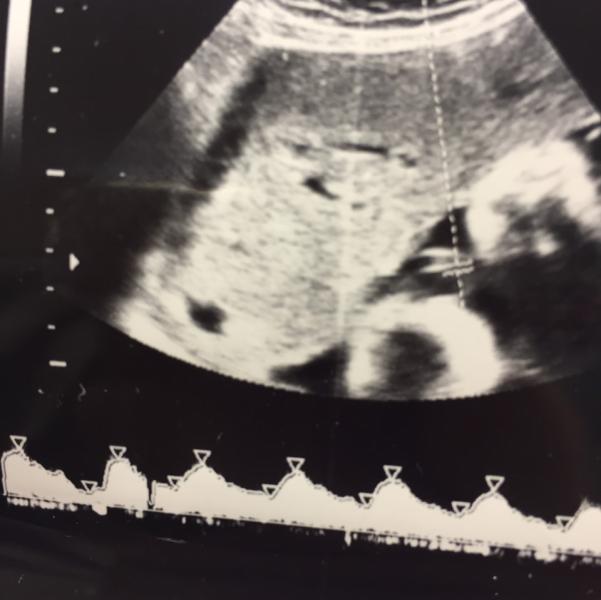

Меня отпустили до завтра. Воды мало, только там где её голова есть вода ито 4 см. Завтра опять на контроль. Будет кесарево у нас. Скорее всего в понедельник. Хоть мама прилетит 😂😂😂 на фото вода между плацентой и малой. Девочки со мной все гуд, слежу за движениями как агент. И знаю что все будет хорошо. Спасибо вам всем❤️💜💗🌺